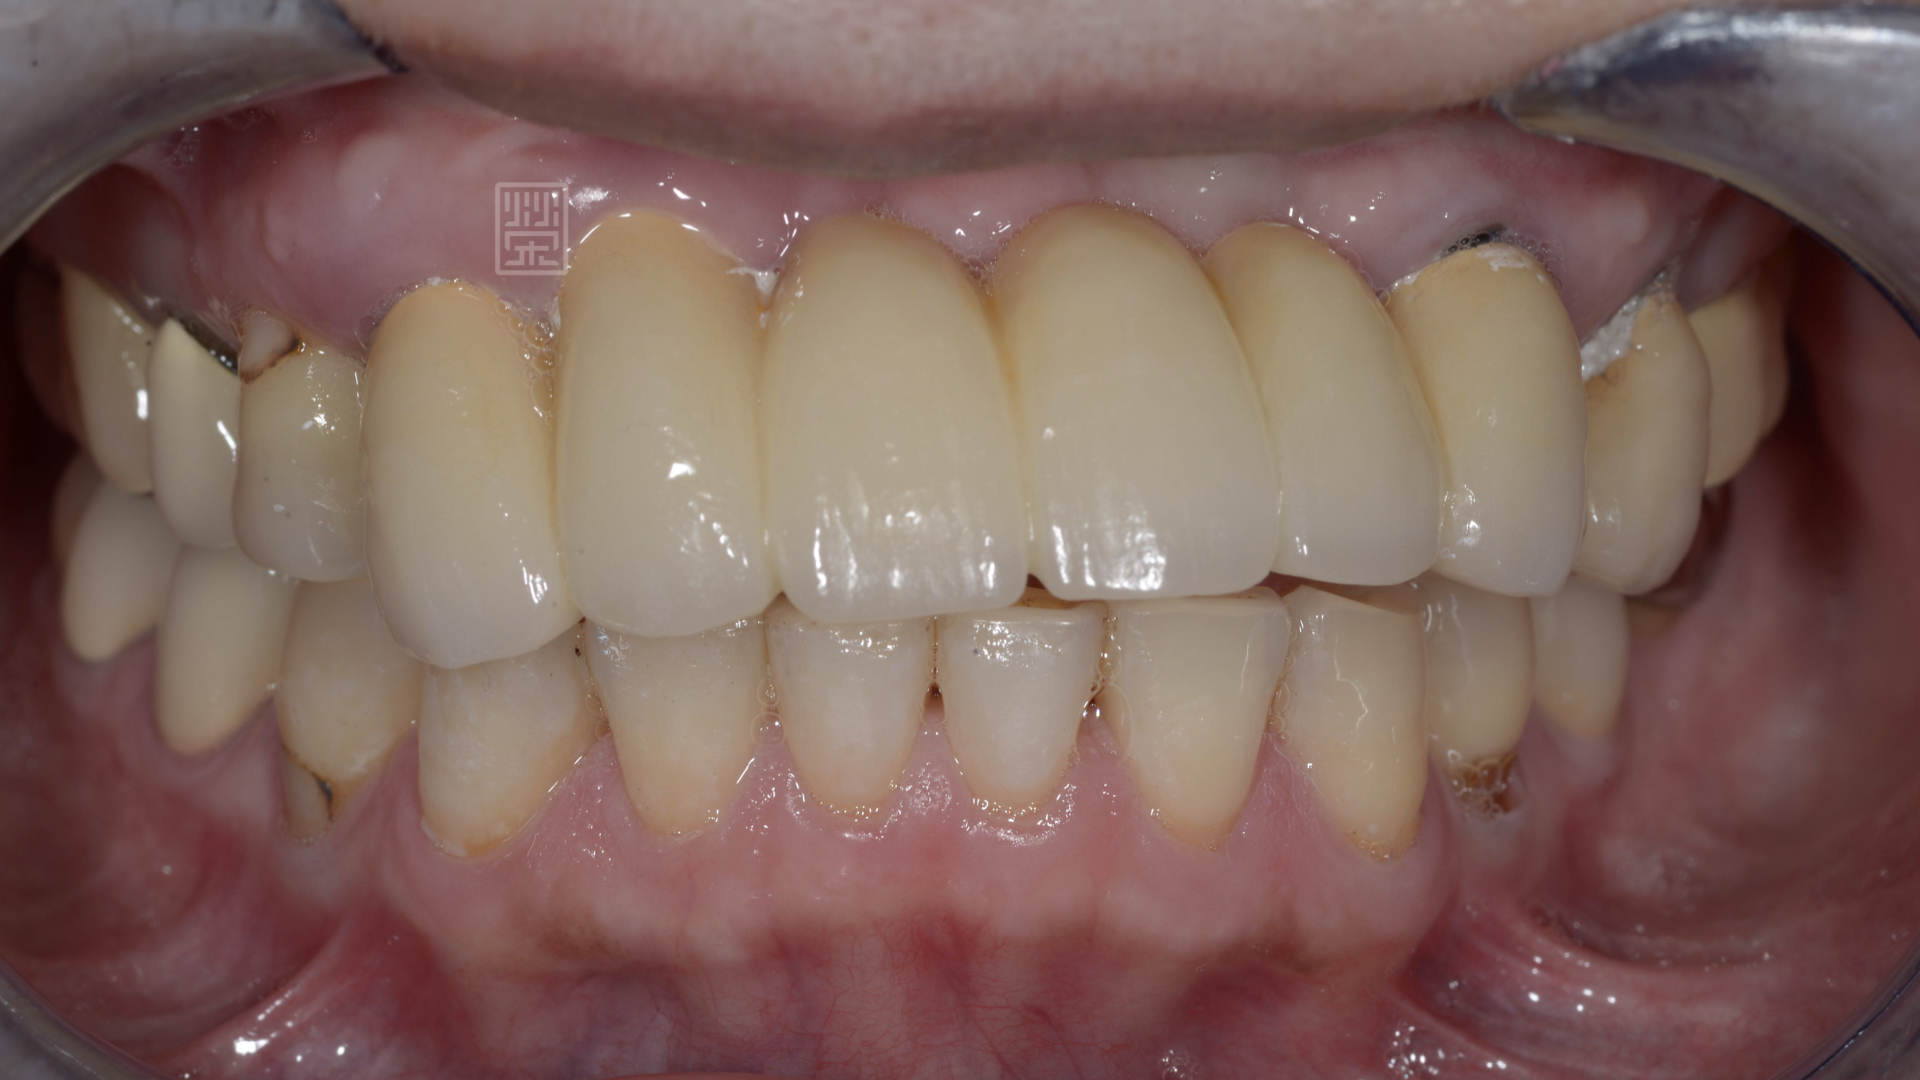

門牙牙齒歪斜,連笑都不敢太大力,怕牙齒會鬆脫

口內檢查發現,牙齒歪斜,咬合開咬,無法有正常的咀嚼功能

口內照片顯示,假牙黏膠未脫落、邊緣不秘貼,無法正常咀嚼及說話